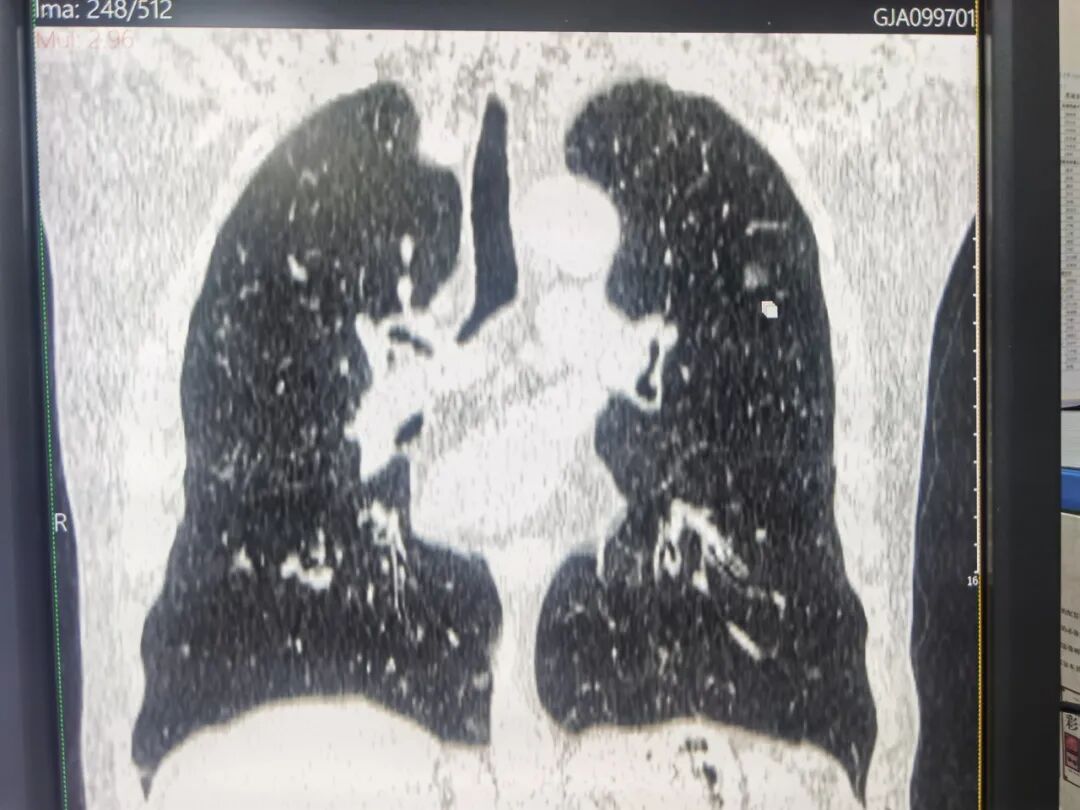

▲图片仅参考,非本文病例